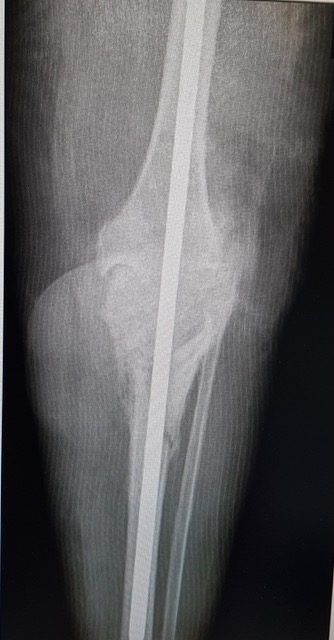

Joi, 9 mai, la Sibiu a avut loc o intervenție chirurgicală complexă, care a presupus un transplat osos. Intervenția s-a desfășurat în cadrul Secției Clinice de Ortopedie a Spitalului Clinic Județean de Urgență Sibiu. A fost vorba despre o artrodeză de genunchi fixată cu tijă centromedulară blocată, care a necesitat transplantul. Potrivit reprezentanșilor spitalului, intervenția a durat mai multe ore și a fost realizată de o echipă formată din Dr. Bogdan Bocea, Dr. Teofil Ispas, Dr. Alexandru Braniște, Asist Mioara Presecan, Asistent Sorin Arcaș și condusă de către Conf. Dr. Mihai Roman. Echipa de anestezie a fost constituită din Dr. Anca Sorea, Dr. Simona Cotor și Asistent Claudia Marcuțiu.

„A fost o operație extrem de complexă, care a solicitat la maxim echipa chirurgicală. Am operat o femeie cu un context medical mai aparte, care a prezentat un defect osos important la nivelul genunchiului, după câteva intervenții chirurgicale/traumatisme din trecut. Intervenția, care a necesitat o pregătire preoperatorie foarte bună, atât medicală cât și administrativă, a decurs foarte bine. Ea reprezintă însă doar o primă etapă în vindecarea pacientei. Urmează o fază postoperatorie dificilă și apoi o recuperare lungă care, speram noi, se va încheia cu un rezultat pozitiv pentru pacienta noastră“, a declarat dl Conf. Dr. Mihai Roman, medic primar ortopedie traumatologie.

Intervențiile de artrodeză a genunchiului sunt operații mai rare și necesită un grad mare de experiență precum si o dotare corespunzătoare. De asemenea, necesită acces la grefele osoase furnizate de către Banca de Os. Operația a fost prima intervenție de acest tip din secția de ortopedie a SCJU Sibiu la care s-a realizat un transplant osos după mai bine de 10 ani. În urma rigorilor impuse de legislația europeană, intervențiile de transplant tisular pot fi efectuate doar în centre special acreditate, procedura de acreditare fiind una deosebit de riguroasă. SCJU Sibiu este acreditat pentru activitatea de transplant tisular – utilizare de țesuturi umane(os/tendon/cartilagii) în scop terapeutic, de către Agenția Națională de Transplant.